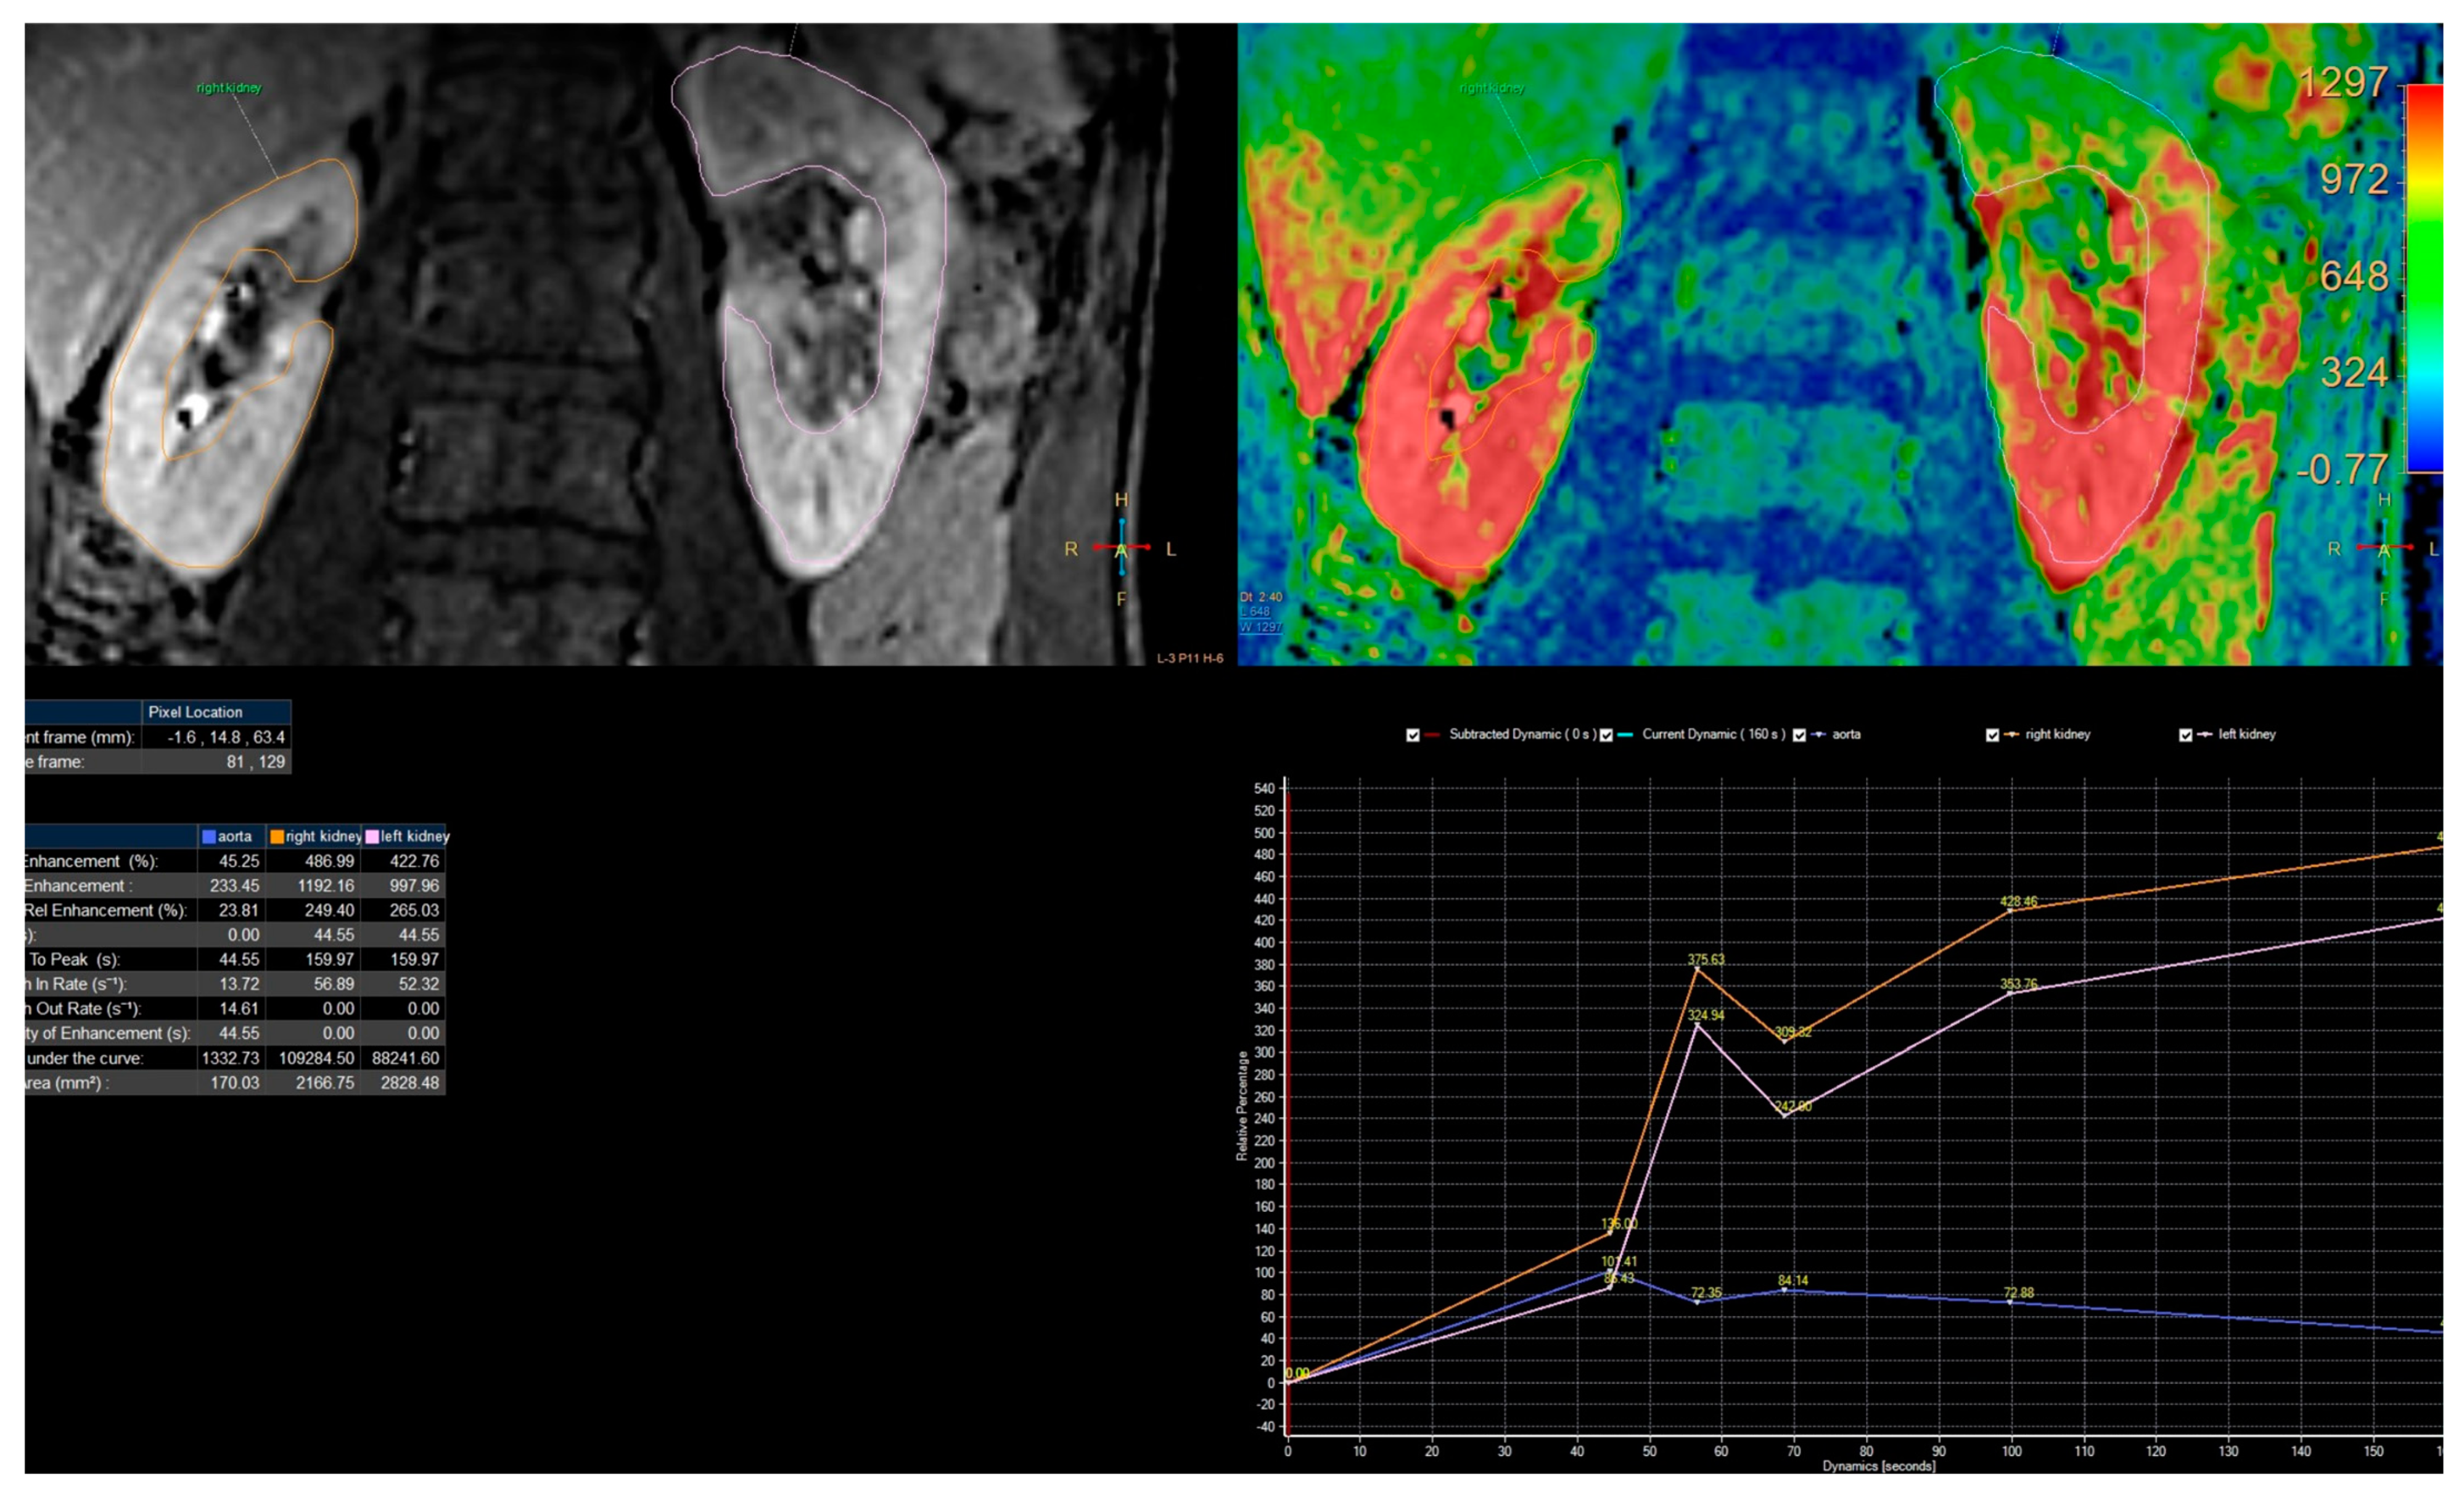

- Separation of the aorta (Figure 3)—the number of time points was found so that the aorta was marked significantly against the background of the organs (the moment of the highest signal intensity in the vessel),

- Separation of the kidneys (Figure 4)—the number of time points was found where contrast is first seen in the calyces,